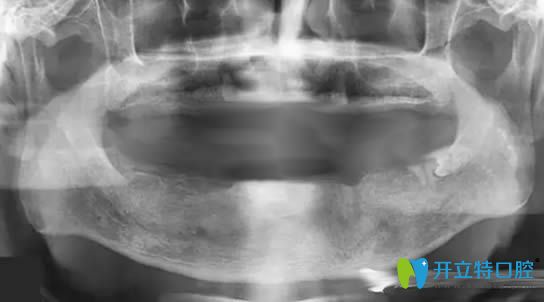

帶10年活動(dòng)假牙萎縮的牙槽骨圖片

牙槽骨萎縮全景片